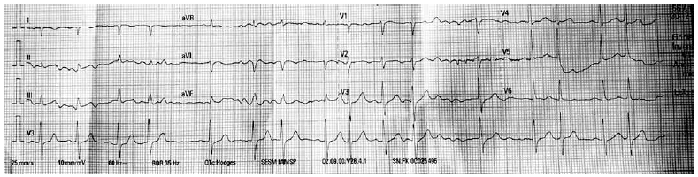

Durante o exame físico, foi observado que o ritmo cardíaco encontrava-se irregular. Foi realizado um eletrocardiograma, mostrado a seguir: